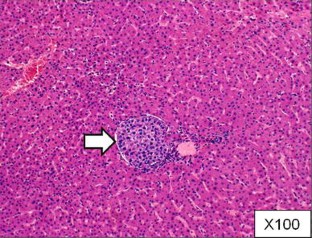

Fig. 1